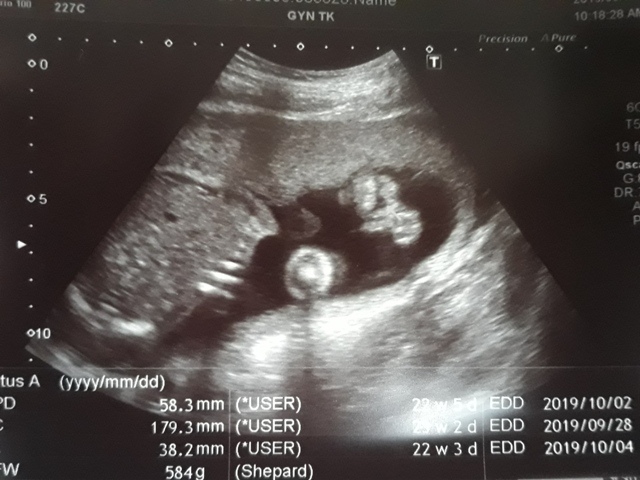

早上十點左右,和小純至澄清醫院做產檢,今日要做的是『妊娠糖尿病』的檢查(一般來說,妊娠糖尿病是24週 - 28週檢查,不過小純今天是第23週又3天,還沒到24週),首先我們先到抽血室去,護理師拿了五瓶裝的美達妍注射液讓小純喝,喝完之後一個小時以後再進行抽血。來之前小純有跟我說過,驗妊娠糖尿病要喝很甜的 糖水,但她今天喝了,感覺還好,不會很甜。

近五次產檢資料統計

| 日期/項目 | BPD | AC | FL | EFW | 心跳 |

| 2019年03月04日 | 無資料 | 無資料 | 無資料 | 無資料 | 無資料 |

| 2019年04月01日 | 28.9mm | 77.9mm | 14.2mm | 107g | 153 |

| 2019年04月29日 | 41.7mm(44%) | 125.7mm(61%) | 28.9mm(103%) | 241g(125%) | 150 |

| 2019年05月22日 | 53.4mm(28%) | 160.6mm(28%) | 34.6mm(20%) | 408g(69%) | 150 |

| 2019年06月03日 | 58.3mm(9%) | 179.6mm(12%) | 38.2mm(10%) | 584g(43%) | 157 |

| BPD:胎兒頭骨橫徑 AC:胎兒腹圍的長度 FL:胎兒大腿骨的長度 EFW:胎兒的體重 括弧內百分比為較上次產檢的成長比例 | |||||

今天關醫師也把4月22日所做的羊膜穿刺及羊水晶片的報告拿給我們,一切都正常。